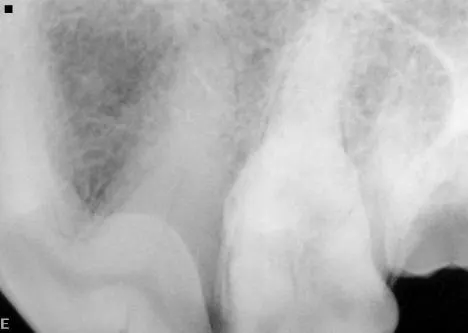

Dental images are best obtained with oral radiography techniques using dental film or a digital sensor and a dental x-ray machine. Locating the dental radiographic unit in the dental operatory makes it quick and easy to take dental radiographs. The film is placed intraorally in most instances to help eliminate overlap of structures. The tube head is manipulated into the correct position for taking the radiograph.

Skulls were used for these images. Dental images were obtained with a digital sensor; the traditional radiographs were taken using extraoral technique with a standard radiographic machine.

A dental radiograph showing the roots of a canine tooth, highlighting the surrounding bone structure and periodontal tissues. The image reveals details of the root canal system and any potential signs of dental disease or abnormalities.

A radiograph displays the lower jaw of a canine, highlighting the alignment and condition of the teeth and jawbone. The image reveals the dental structure, including the roots and crowns of the teeth, providing insights into potential dental issues.